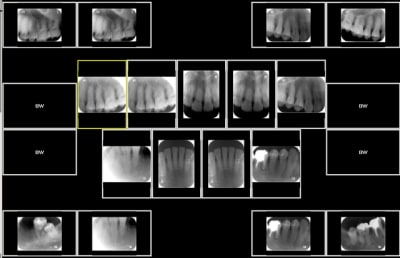

Voila un exemple, visiodent en duplique certaines sur le status perceque je note plusieurs dents sur chaque cliché. Y'en a 10 uniques en tout. Excusez la qualité, c'est paint...

Exemple status k4v0je - Eugenol

mais comme tu le vois j'ai pas besoin de plus de clichés, enfin je ne pense pas?